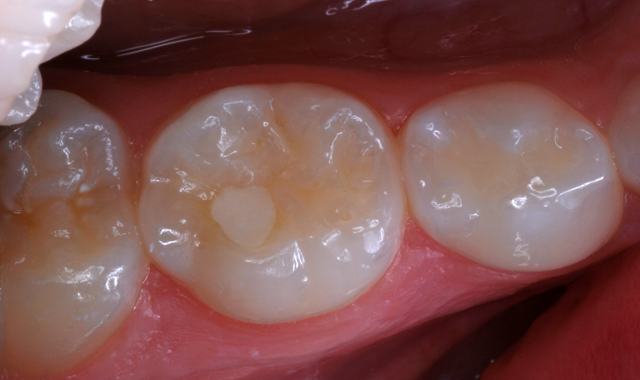

Once set, the material was ready for finishing (Fig. 11). A large round bur at slow-speed trimmed excess material from the margins (Fig. 12). With the rubber dam still in place, polishing was completed with a 3M™ Sof-Lex™ Diamond Polishing System wheel (Fig. 13).

After removal of the rubber dam, occlusal contacts were evaluated. The Ketac Universal restoration is shown seven weeks postoperatively (Fig. 14).

Fig. 13 Fig. 14